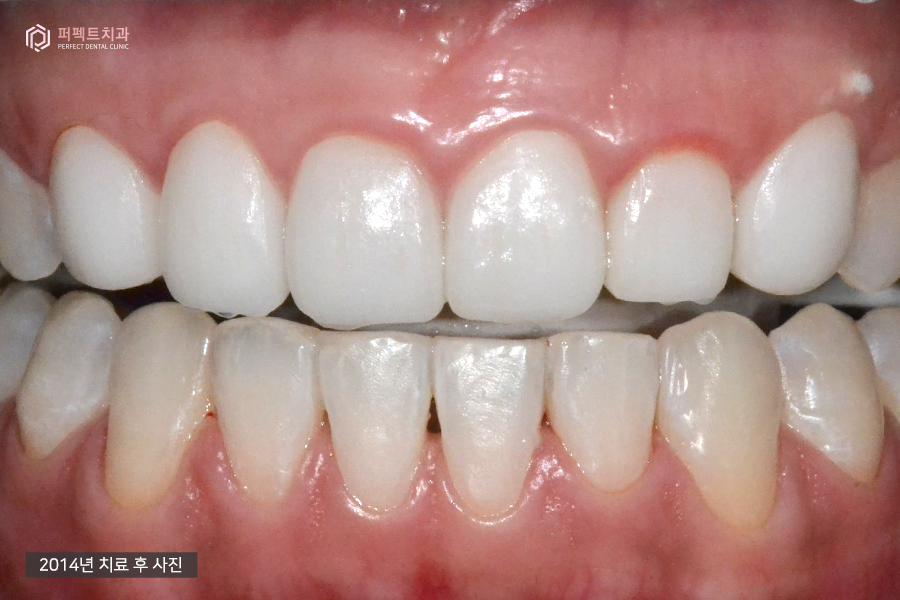

(왼)2014년 사진 / (오)2021 사진

교정 후 라미네이트로 마무리까지 한 사진입니다. 이 사진은 2014년도(왼)와 7년이 지난 2021년도(오) 사진인데 약간의 변색이 있는 치아 외에는 아주 잘 유지되고 있는 상태였습니다.

오늘은 충치치료부터 부분교정, 라미네이트 그리고 유지장치까지 쭉 치료가 이어진 경우인데요. 마무리가 잘 되었고 총 치료기간은 4개월 미만이었습니다.